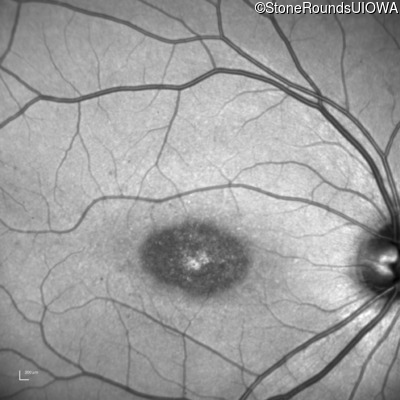

Infrared Fundus Photograph - Right - 20/125 sc

Exemplar